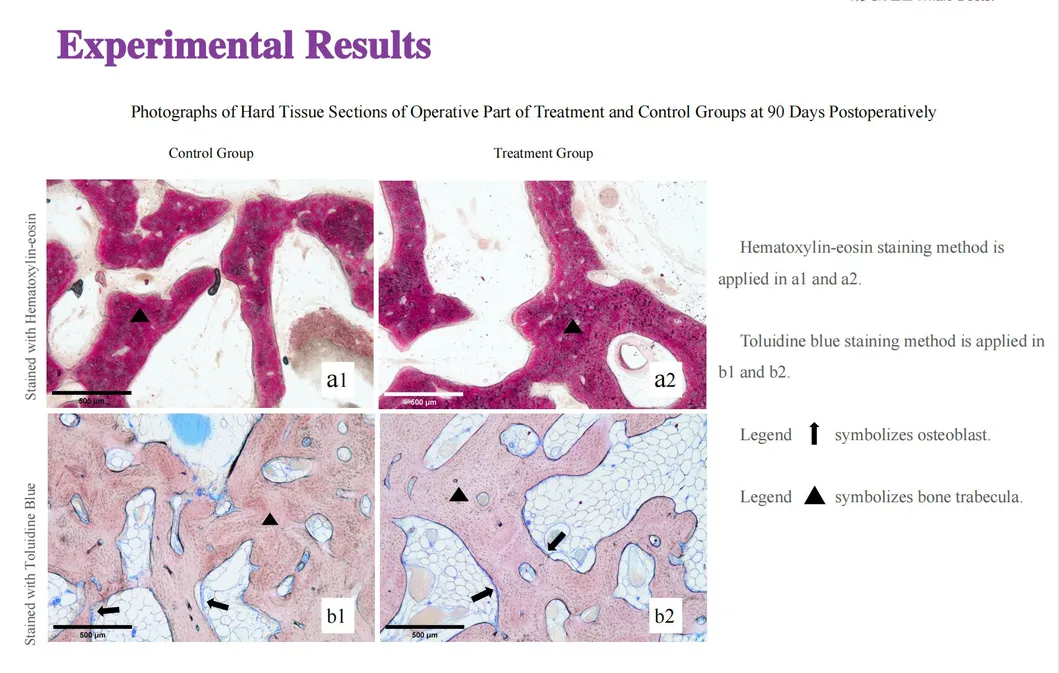

In this groundbreaking study, dogs were selected to assess the effectiveness of the Golden Cudgel-Pneumatic Dental Elevator Kit. Researchers meticulously documented physiological parameters, extraction duration, and socket damage compared to traditional manual devices. The data provides profound insights into the superior performance and efficiency of these advanced dental tools.